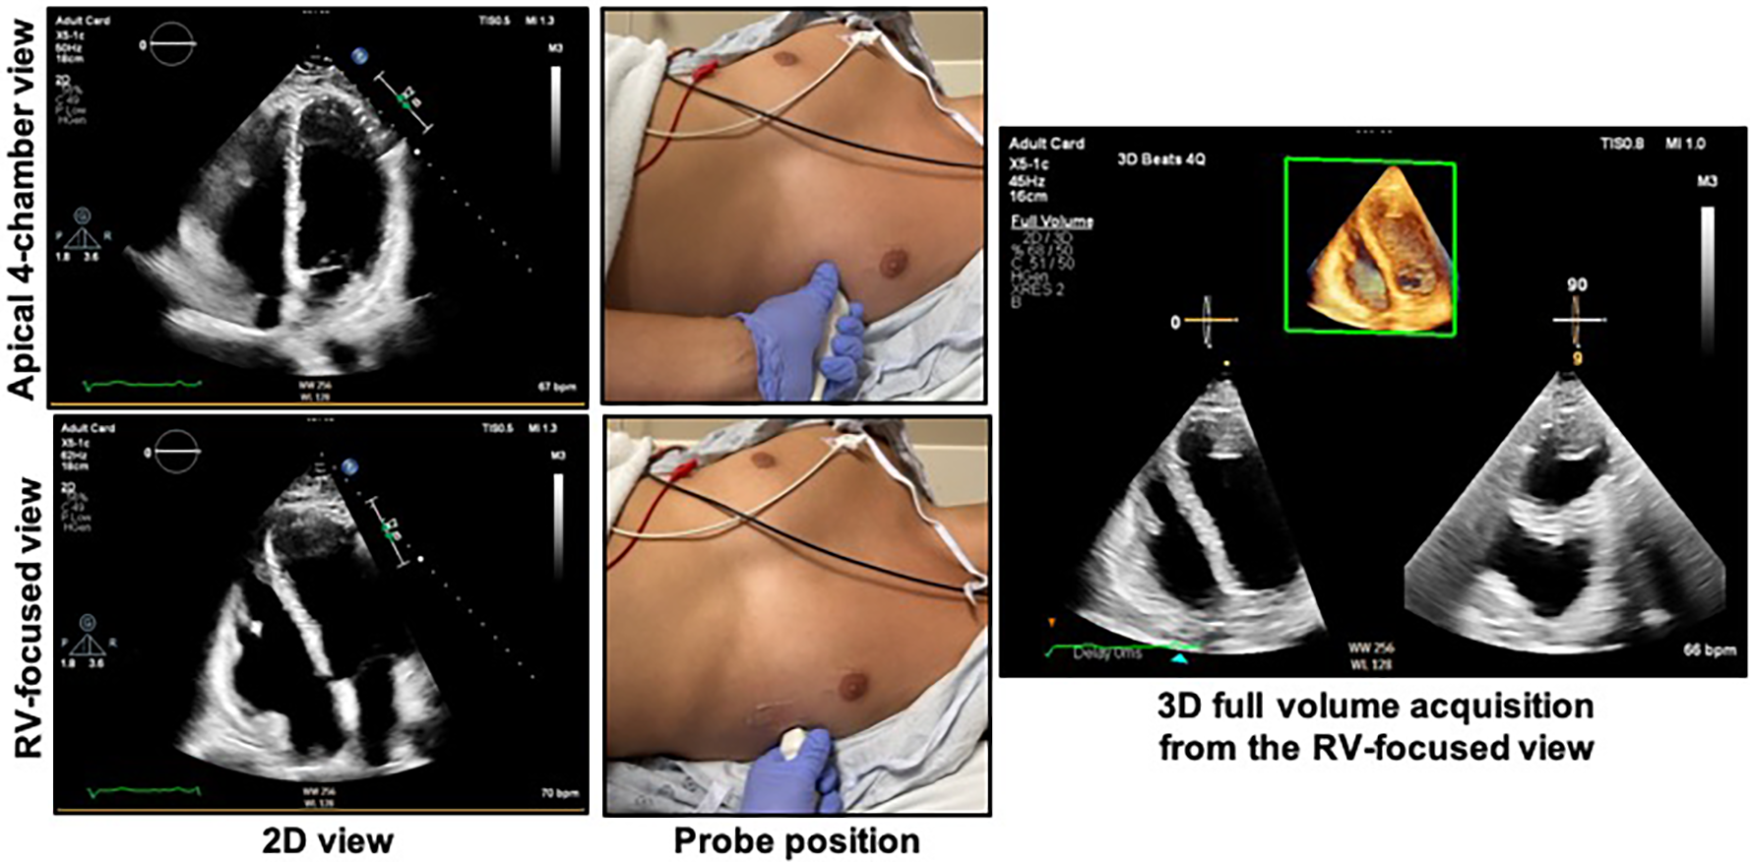

Figure 4

Obtaining the right ventricular focused view. The patient should be in the left lateral decubitus position with the left mid-clavicular, fifth intercostal region (approximate apex of the heart) positioned over the cut-out area of the bed if available. The top right shows the apical 4-chamber view as acquired from the probe position at top middle. The bottom left shows the RV-focused view as acquired from a more lateral location as shown in the bottom middle panel. The 3D dataset should be acquired from the RV-focused view to maximize capture of the RV free wall. See Figure 5 for the characteristics of an optimal 3D dataset. RV, right ventricle.